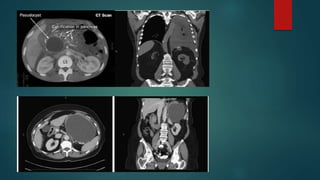

3.Pancreatic pseudocyst

 By definition, the capsule of a pseudocyst is composed of collagen and

granulation tissue, and it is not lined by epithelium.

location-Lesser peritoneal sac in proximity to the pancreas Large pseudocysts

can extend into the paracolic gutters, pelvis

Pathophysiology

 Pancreatic necrosis causes ductular disruption, resulting in leakage of

pancreatic juice from inflamed area of gland, accumulates in space

adjacent to pancreas Inflammatory response induces formation of distinct

cyst wall composed of granulation tissue, organizes with connective tissue

and fibrosis

 5% to 15%